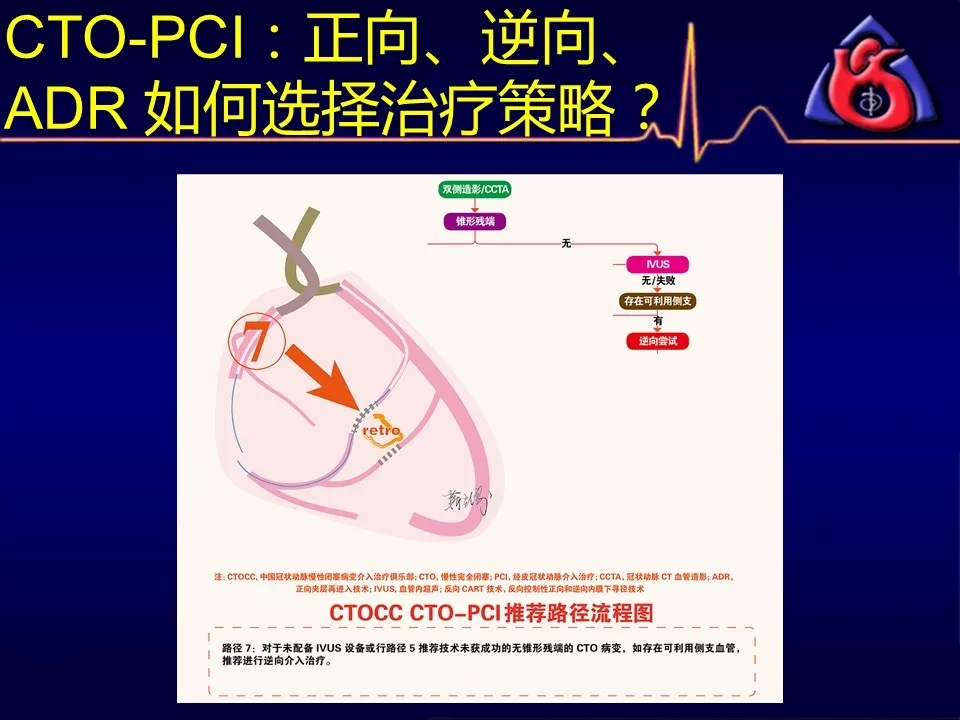

如何选择正向、逆向、IVUS指引及ADR技术?

逆向技术无条件(无可利用侧枝血管)